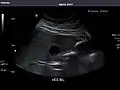

Aorta: Visualized portions normal in caliber, 16 x 15 mm.

Aorta